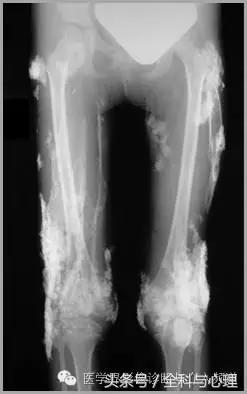

一、肿瘤样钙质沉着症

累及多个关节,范围较大,表现为多房囊状的高密度影。

原发性:罕见,多为家族性,多见于非洲裔美国人,钙磷正常。

继发性:多见于慢性肾功能不全患者。钙磷均有升高。

肿瘤样钙质沉着症